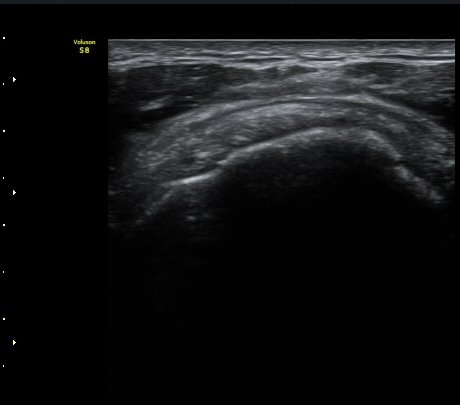

ÀÌµÎ¹Ú±Ù°Ç È¾´Ü¸é°Ë»ç¿¡¼­ ƯÀÌ ¼Ò°ßÀ» º¸ÀÌÁö ¾ÊÀ½(»çÁø 1, 2).